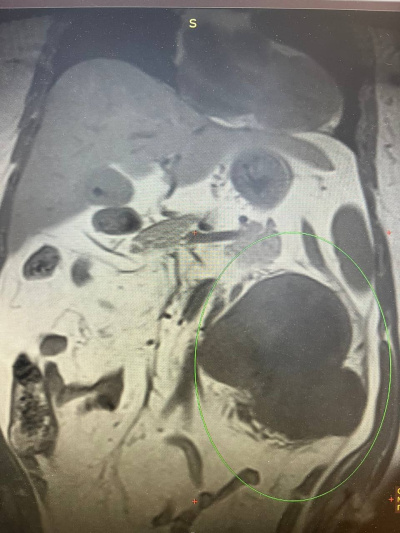

Ситуация осложнилась ещё одной диагностической "находкой" – единичным метастазом опухоли в лёгких.